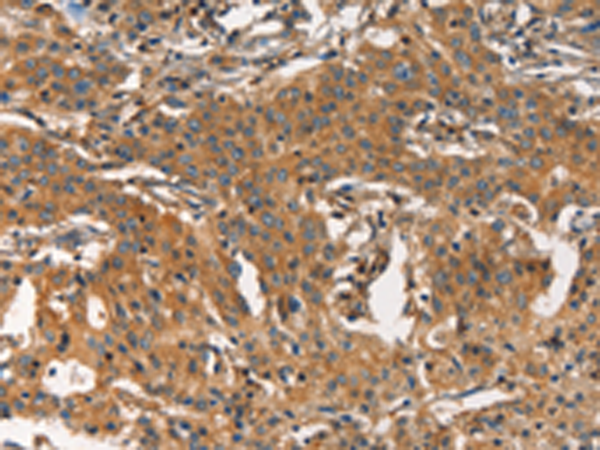

分类: 科研抗体货号: P11181别名: AMD; SAMDC; ADOMETDC应用: IHC反应种属: Human, Mouse, Rat